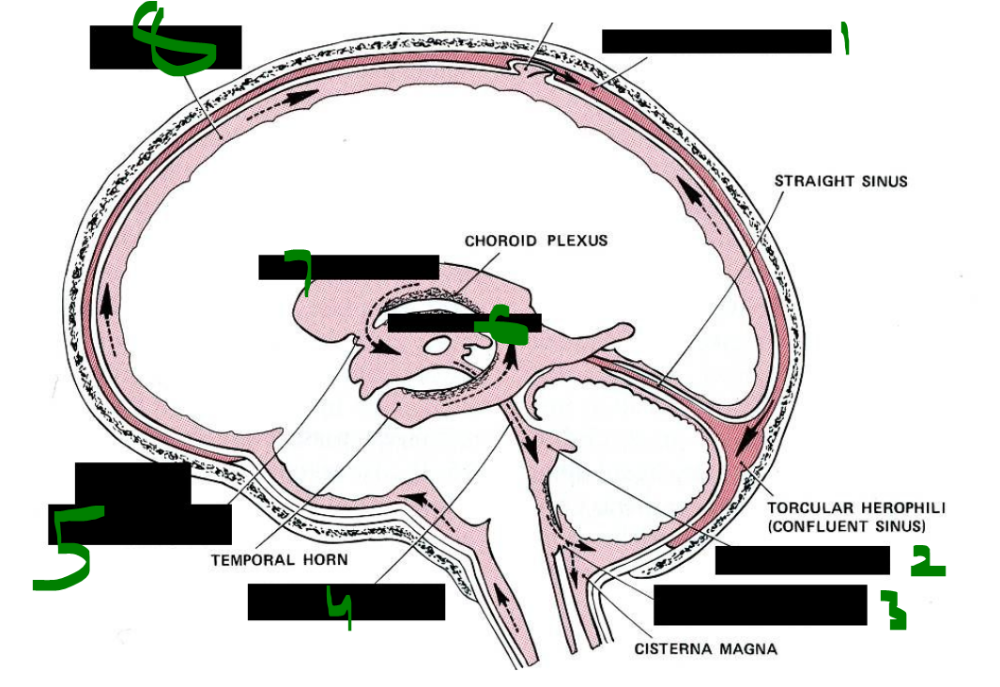

What is 1?

intracranial parts

73

card image

What is 2?

basilar artery

74

internal carotid a.

vertebral a.

72

What is 3?